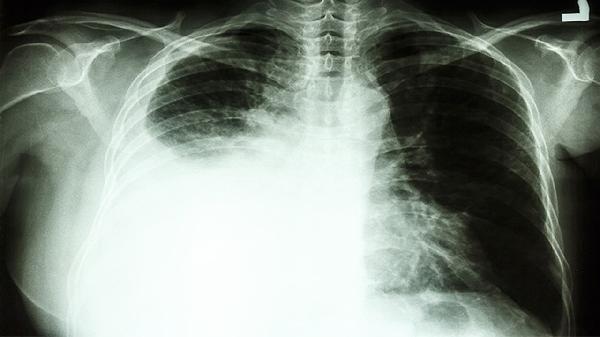

需要明确的是,肺癌的治疗效果受多种因素影响,包括病理类型、分期、基因突变状态等。单纯依靠安康欣胶囊难以达到理想的治疗效果。中晚期肺癌患者更需优先考虑靶向治疗、免疫治疗等现代医学手段。该药物使用过程中可能出现胃肠道不适等不良反应,与其他抗肿瘤药物联用时更需谨慎评估。